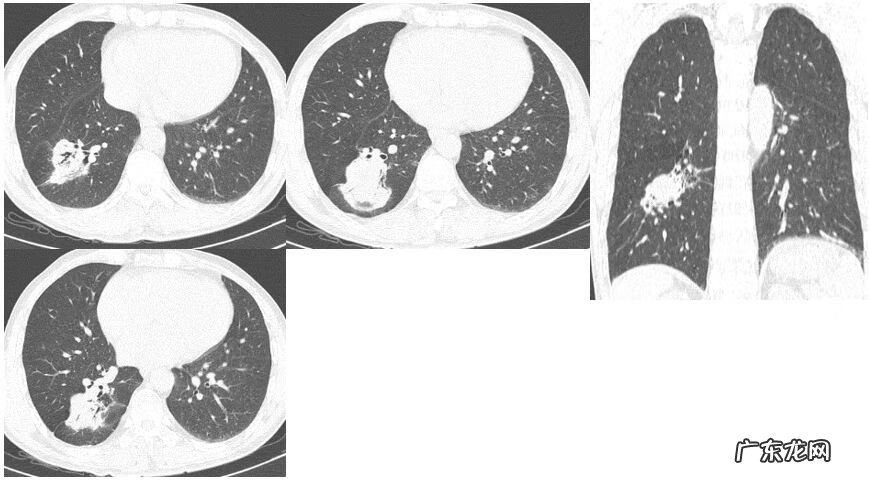

非典型表现——肿块型

孤立性肿块型在临床非常难以鉴别,我只是把自己的经验和大家分享 。肿块型好发于外周,右肺下叶较多见;尖角征,周边伴毛刺及索条,周围伴有磨玻璃密度影;病灶内可见坏死和空洞,空洞较小,内壁光整;内有支气管气相及空腔;病灶临近胸膜时,与胸膜呈宽基底相连,胸膜可增厚粘连,胸膜下脂肪层存在 。